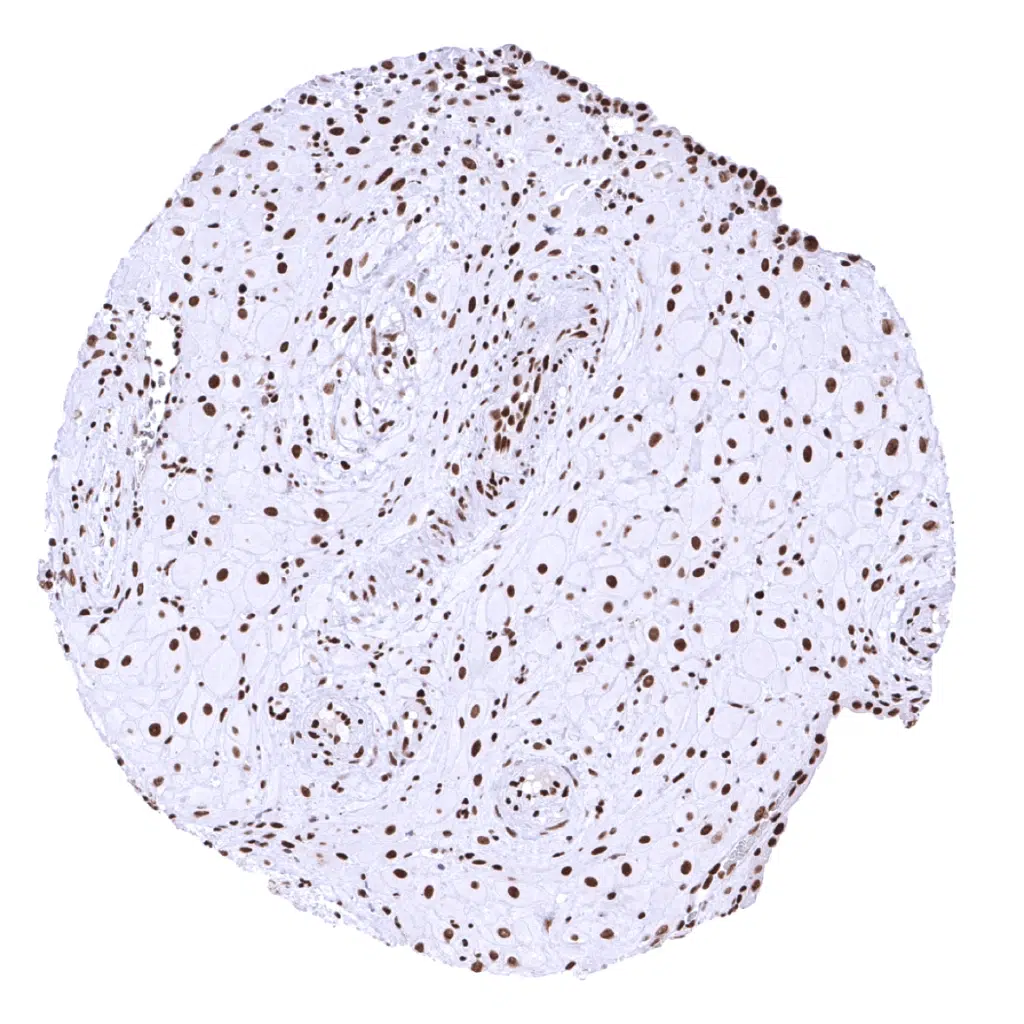

Adrenal gland